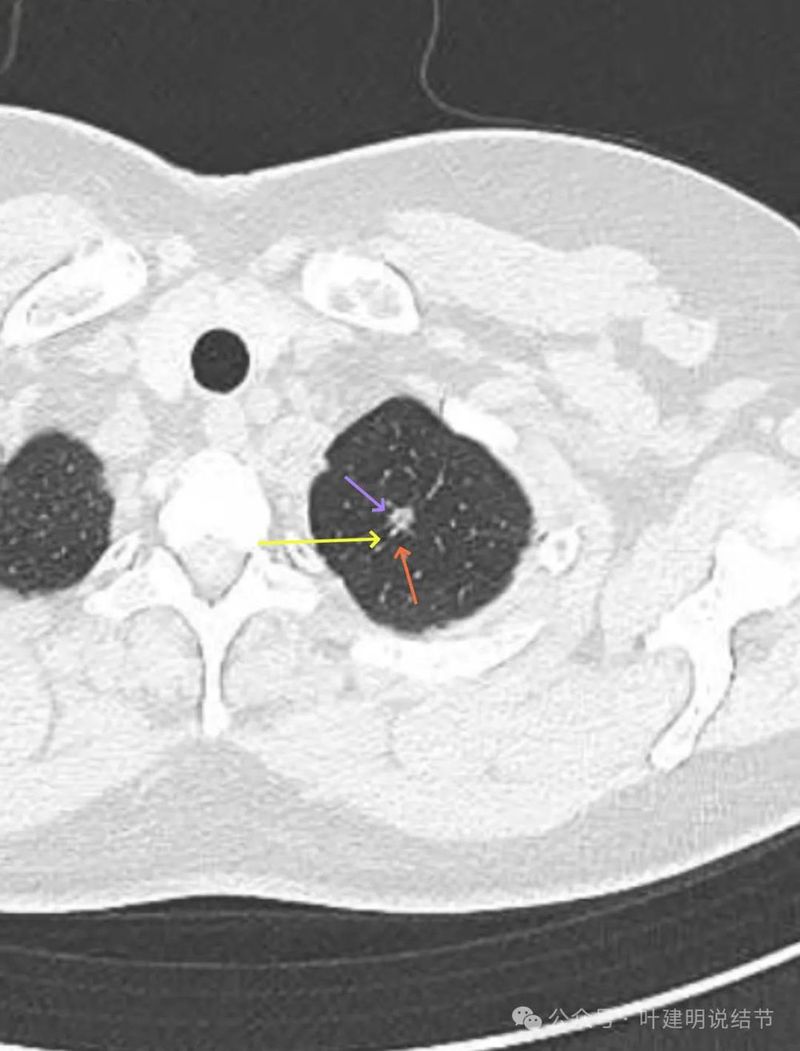

灶内见到血管穿行,整体轮廓清楚,密度欠均。

有明显磨玻璃成分,有血管紧贴,有小血管穿行,整体轮廓与边界清。

整体密度较高,有血管贴着,边缘少许磨玻璃成分。